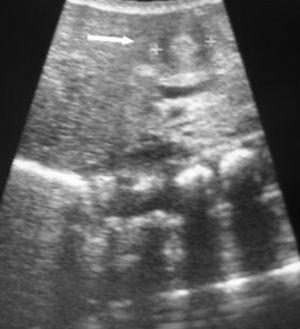

Se presenta el caso de un recién nacido varón fruto de una gestación espontánea y a término en una madre de 19 años. En la ecografía gestacional realizada en la semana 33 se detecta la presencia de gastrosquisis fetal. En los controles ecográficos posteriores se comprobó que la malformación se mantenía estable y se decidió mantener una actitud expectante hasta finalizar el parto por cesárea en la semana 40 de gestación. Al nacer el paciente pesó 2.305 g (p < 10), e inmediatamente se realizó aislamiento y humidificación de las asas evisceradas durante 24-48 h, procediendo posteriormente a la intervención quirúrgica. Tras realizarse ésta con éxito, el paciente precisó analgesia, sedación profunda y ventilación mecánica durante 3 días, nutrición parenteral exclusiva 7 días, comenzando entonces la alimentación enteral con leche materna (LM), administrada por sonda orogástrica (SOG), presentando intolerancia alimentaria y vómitos. A los 13 días de vida, por persistencia de la clínica digestiva, se realiza radiografía de abdomen que muestra dilatación inespecífica de las asas intestinales, iniciándose tratamiento con domperidona vía oral, 0,3 mg/kg/dosis cada 6 h. Tras presentar una mejoría inicial, reaparece la clínica, y es cuando se realiza el tránsito esofagogastroduodenal, objetivándose un stop a nivel del antro. Ante la sospecha de membrana antral se estudia mediante gastroscopia evidenciándose estenosis y dificultad para el paso transpilórico del gastroscopio. Tras descartarse la sospecha diagnóstica de membrana antral y pensando entonces en una compresión extrínseca, se lleva a cabo estudio ecográfico que muestra una estenosis hipertrófica del píloro (fig. 1). El paciente es intervenido a los 28 días de vida mediante piloromiotomía extramucosa según técnica de Ramsted. Es a partir de este momento cuando se produce una mejoría clínica digestiva con tolerancia adecuada a volúmenes de LM cada vez mayores. Nuestro paciente fue dado de alta a los 45 días de vida con un peso de 2.900 g (p < 3) pero con un buen estado general y asintomático. Durante el seguimiento hasta los 4 meses de vida los controles analíticos han sido normales, con curva pondoestatural ascendente.

Figura 1. Imagen ecográfica de estenosis hipertrófica de píloro.